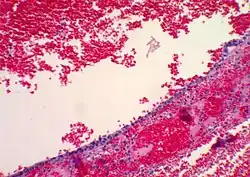

Histopathology

In case an ovarian cyst is surgically removed, a more definite diagnosis can be made by histopathology:

| Type | Subtype | Typical microscopy findings | Image |

| Functional cyst | Follicular cyst |

|

| Corpus luteum cyst |